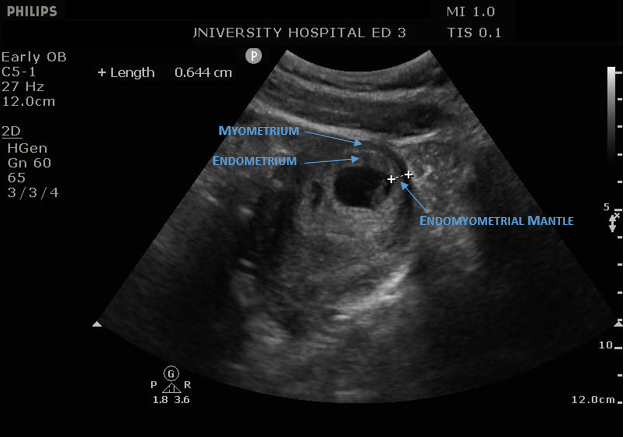

Read MoreCharacterizing location of an intrauterine pregnancy is a key portion of the sonographic exam in early gestation. In this month’s case Dr. Leech describes a case concerning for lower uterine gestation, as well as the diagnostic and therapeutic considerations for this pathology.

Read MoreThis is our inaugural edition of the Ultrasound Case of the Month. In this case we examine an early pregnancy ultrasound with an unusual finding. Read on to learn about a measurement we are often not doing in the ED and what we may be missing.